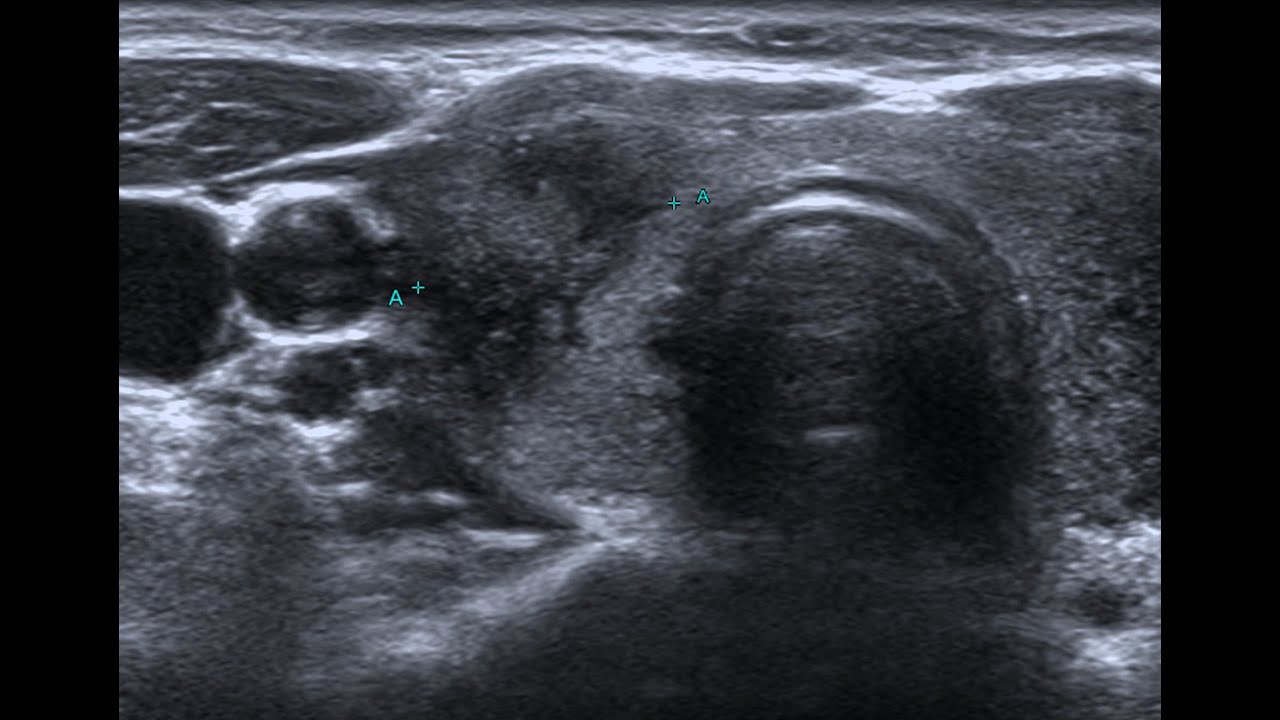

THYROID CANCER DIAGNOSIS - My story

Описание: Today I share the lead up to my Stage 3 cancer diagnosis, and the suggestion treatment on thyroidectomy, neck dissection, jugular vein removal and radioactive iodine.

In 2021 I was diagnosed with Stage 3 Thyroid Cancer, and after surgery have chosen to heal cancer naturally. I share my journey on here, along with kundalini meditations and holistic health tips.